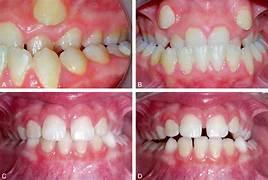

Latérodéviation Mandibulaire Sévère

Définition

Déformation structurale dissymétrique ayant pour conséquence une déviation du milieu incisif inférieur d’origine squelettique. Elle est caractérisée par :

- Retentissement facial avec convergence des lignes horizontales (bi-sourcilière, bi-pupillaire, bi-commissurale) vers le côté atteint.

- Déviation latérale permanente du corps de la mandibule.

- Occlusion inversée unilatérale.

- Milieux incisifs déviés en ICM et en RC.

Image : Latérodéviation mandibulaire.